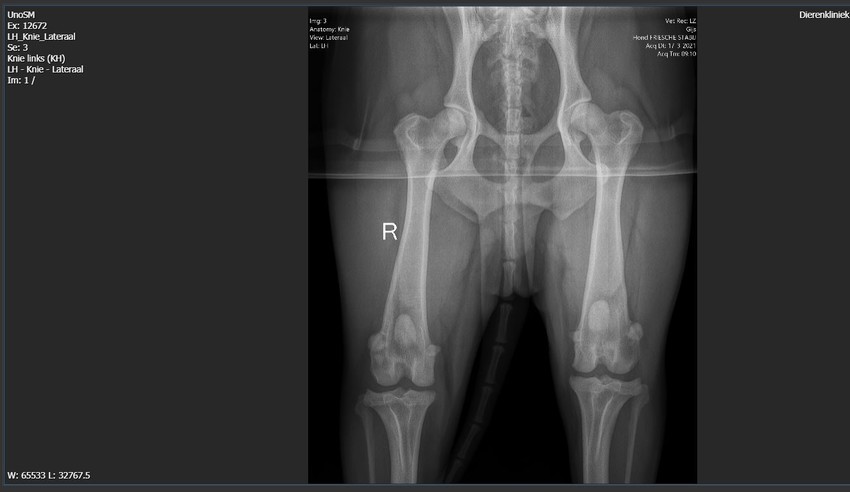

Aangezien ik natuurlijk wel nieuwsgierig was naar de foto's heb ik deze opgevraagd bij de dierenarts

De foto's van de eerste keer, van onder andere de schouders, heb ik ook nog gevraagd

Nou ik heb de rest van de foto's die eerder al gemaakt waren ook ontvangen

Aangezien links en rechts overal gelijk is zal ik ze niet allemaal plaatsen

Elleboog rechts, waar dus wel iets artrose zit. Links zit evenveel